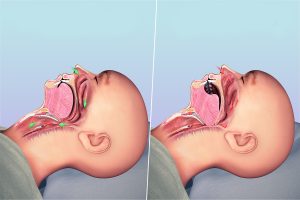

Obstrüktif yani tıkayıcı uyku apnesi türünde hastanın boğaz ve çevresindeki yumuşak dokular hava yollarının tıkarken; merkezi uyku apnesinde hava yolu tıkanmaz ancak beyin solunum sistemine sinyal iletimini başaramaz.

Her yaştan kişide görülebilen uyku apnesi sendromunun temel nedeni boğaz kaslarının solunum yolunu tıkayacak denli gevşemesi olarak belirtilebilir.

Uyku apnesinin belirtilerini engelleme noktasında az önce sayılan yöntemlerden hiçbiri işe yaramazsa solunum sorunlarına neden olan problemlerin giderilmesi için cerrahi yöntemlere başvurulabilir.

Bu kapsamda fonksiyonel rinoplasti, septoplasti, dil köküne yönelik ameliyatlar veya hava yolunu genişleten operasyonlar hastaya önerilebilir.